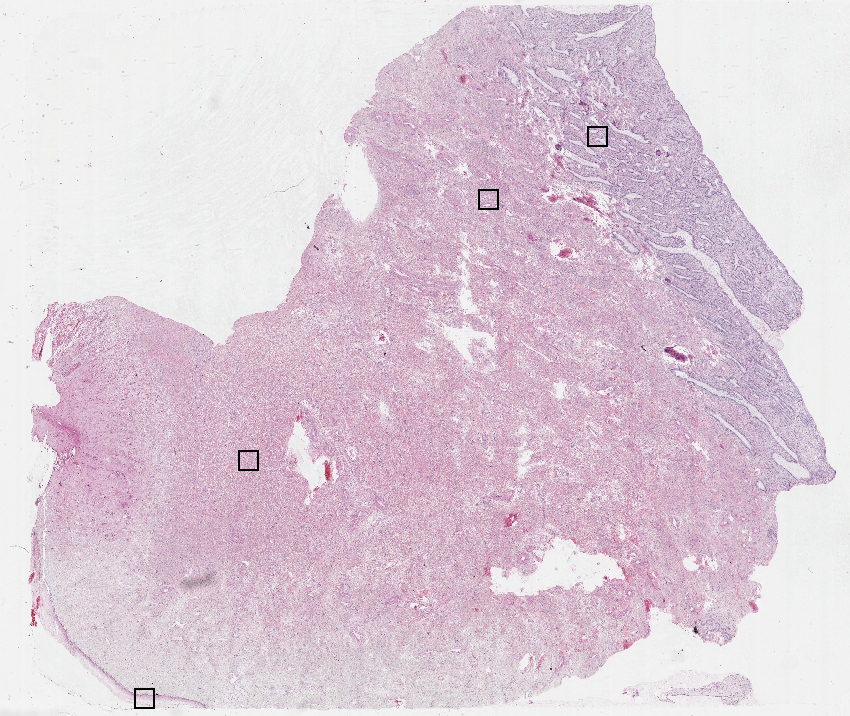

Cell types%

Glandular cells:

10

Squamous epithelial cells:

5

Smooth muscle cells:

65

Other cell types:

20